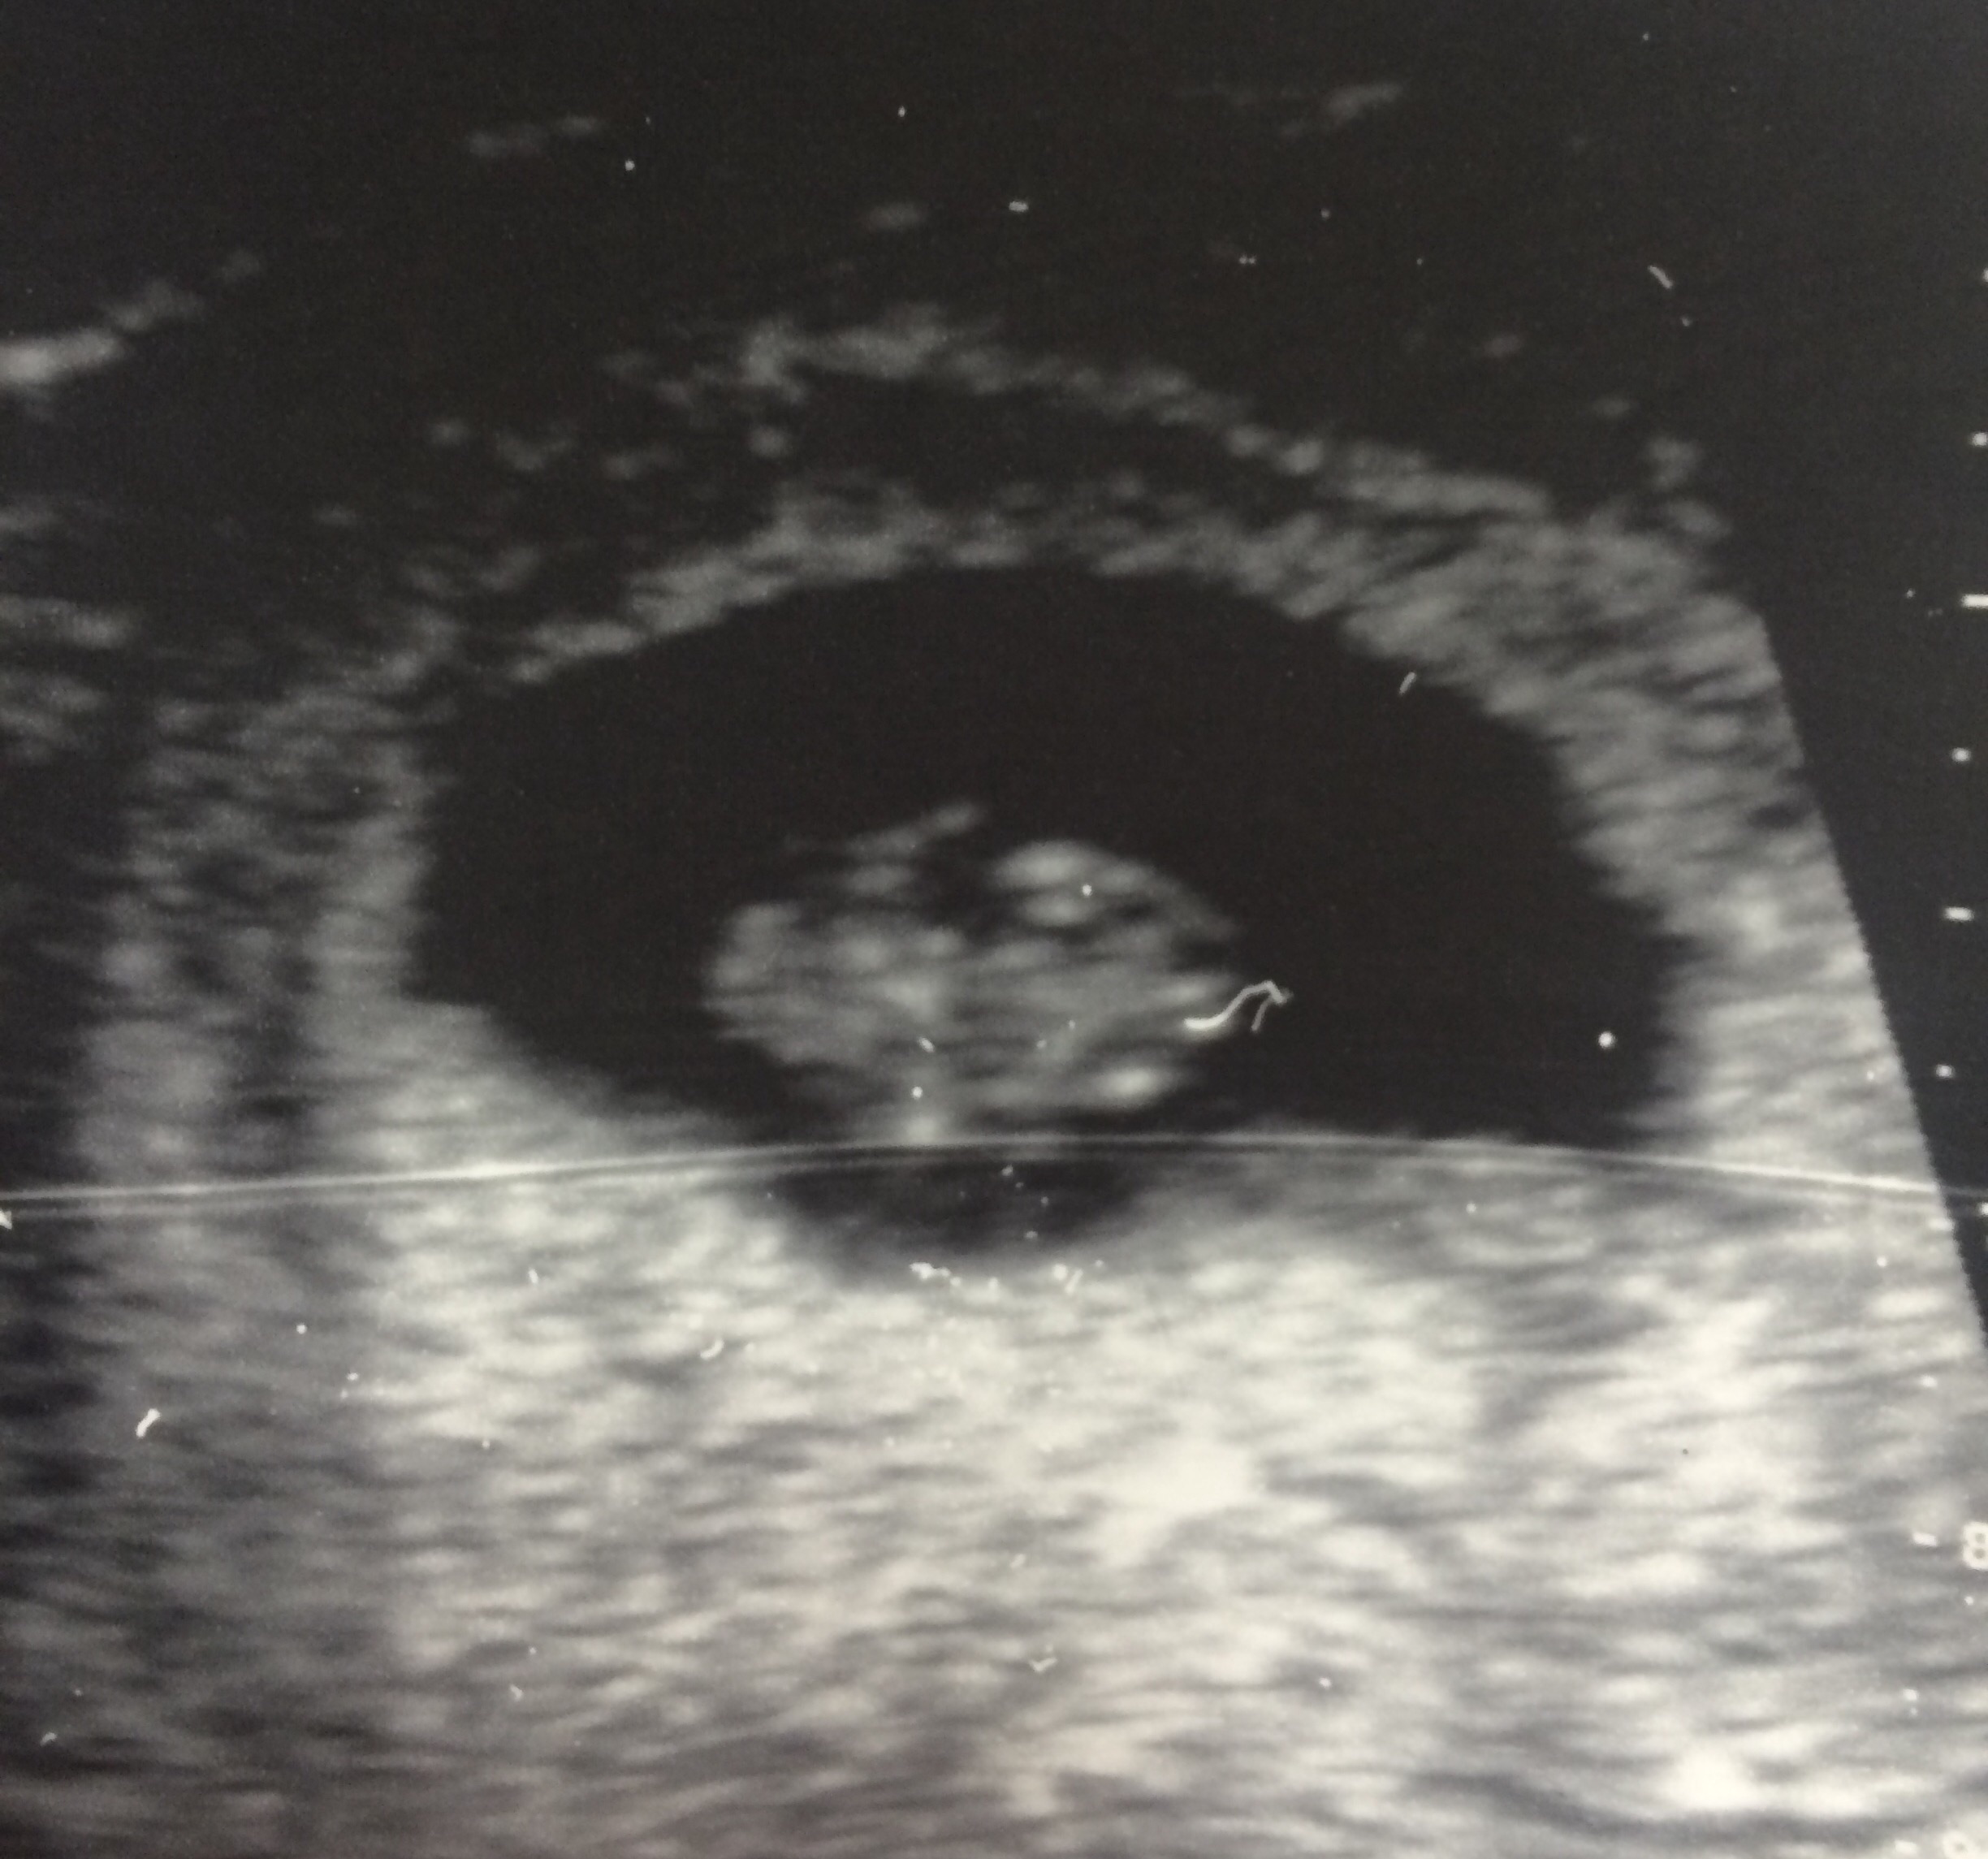

Houston, we have a heartbeat!

Hi everyone! Just had my first ultrasound and was so excited that I thought I'd share on here since we aren't telling people yet. The tech couldn't tell me much but my due date moved from April 6 to 9 (ughhhh). Is that normal? We got to see the little heartbeat which filled me with so much joy and relief. Here's our little blob!

image